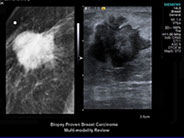

• Ultraschalluntersuchung der Brust